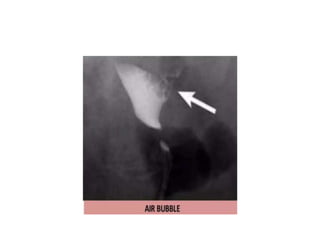

• Care taken to expel all air bubbles from syringe/cannula

• TECHNIQUE • Thept is placed supine with knees flexed and legs abducted • Vulva cleaned with chlorhexidine or saline. • Speculum is then placed using sterile jelly and cervix is exposed. • Hsg canula/ cathetor is inserted in to cervical canal (vulsellum forceps to hold the cervix) • Care taken to expel all air bubbles from syringe/cannula • Spasm of the uterine cornua relieved by intravenous glucagon